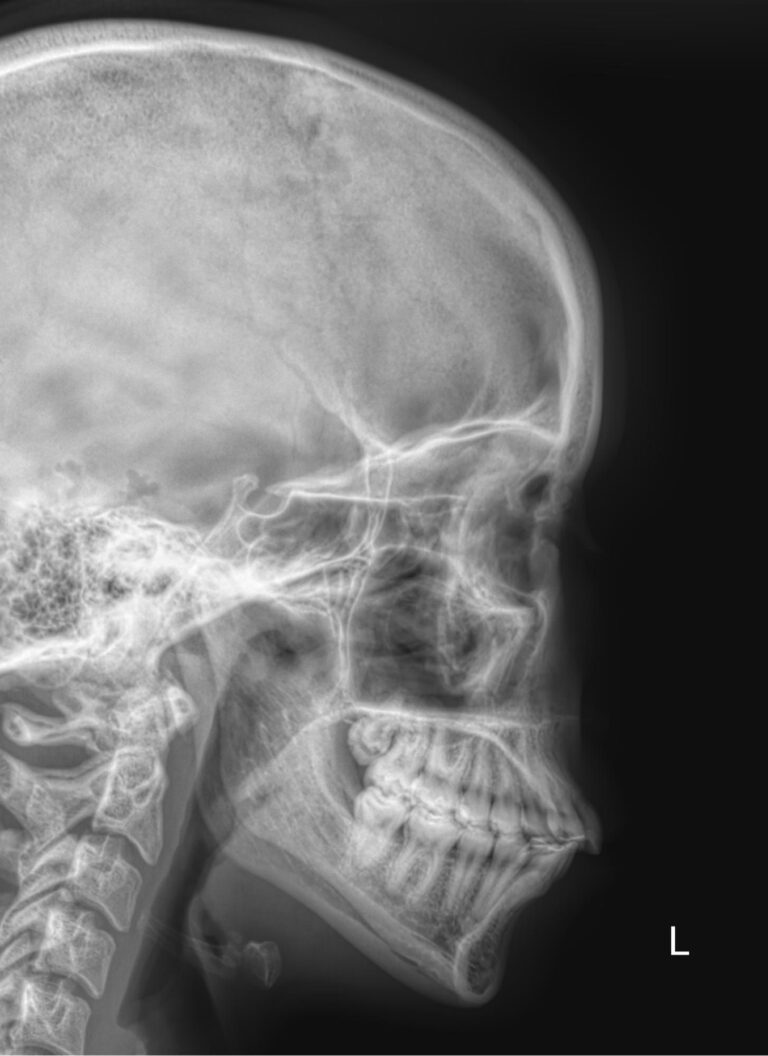

Придаточные или околоносовые пазухи носа ― это система воздухоносных полостей, располагающихся в костях черепа. Пазухи или синусы увлажняют и согревают вдыхаемый воздух, участвуют в формировании голоса, делают кости лица более легкими и смягчают силу удара при травме. К пазухам относятся:

Не всегда патологии синусов протекают с ярко выраженными симптомами, но даже малейшие изменения отчетливо видны на рентгеновском снимке. Поэтому рентгенография ― первый и, часто, окончательный метод обследования. Современные рентгеновские аппараты, по сравнению с оборудованием предыдущего поколения, не несет такой мощной лучевой нагрузки. И позволяет выполнять серию снимков как в начале лечения, так и в процессе подготовки к операции или для определения эффективности терапии.

• Носовая перегородка ― прямая, искривленная, утолщенная;

• Носовые ходы ― свободны, сужены;

• Контур слизистой внутри пазух ―слизистая  обычная, утолщенная, есть рубцевания;

• Внутренние контуры ― четкие, расплывчатые;

• Наличие воздуха ― пневматизация сохранена, снижена;

• Жидкость ― в норме быть не должна, но если она есть, будет виден ее уровень;

• Новообразования;

• Инородные тела.